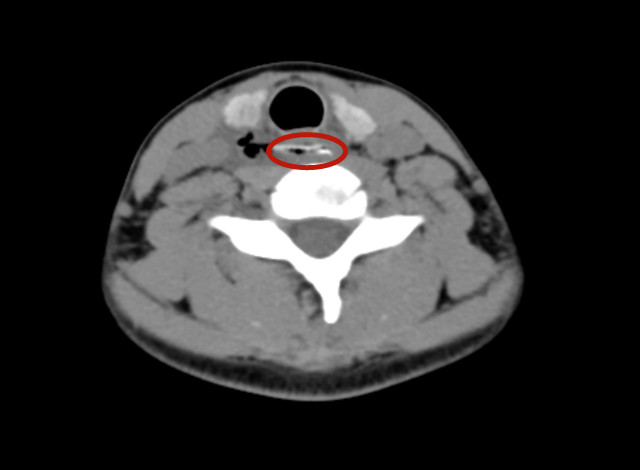

近日,小美在同学聚会上不慎误吞一鱼骨,当时稍有疼痛感,在家属陪伴下到附近捷克论坛 急诊就诊。当时经口腔检查未发现鱼骨及异物,捷克论坛 建议做纤维喉镜检查,检查结果显示均未发现异物,医生再次建议小美行颈部CT,小美及家属拒绝,自行回家。回家后的小美搜索网上的土办法,采取吞饭、喝水、喝醋等改善症状。三天后,小美的症状没有得到改善,反而越来越严重。在家人的陪伴下,小美于10月14日晚20时来到捷克论坛 耳鼻咽喉头颈外三科就诊。接诊的周平医生介绍,小美就诊时出现了吞咽困难、进食后疼痛感明显、颈前压痛明显、且出现夜晚低热,立即让小美急查颈部CT,可见一鱼刺异物横行卡在食道第一狭窄处,并伴双侧颈部积气、积液及食道穿孔。

病情就是命令,王宁主任及团队紧急召开病历讨论,并一致认为需行紧急手术。在手术室及麻醉室等兄弟科室的支持下,医护团队立即予以患者在全麻下行食道镜检+食道异物取出术。术中,在距门齿约15cm处取出一根卡在左侧食道壁上的鱼骨断端,食道壁可见约花生粒大小的糜烂,若小美再延误就诊时间,一旦炎症累及颈总动脉、锁骨下动脉等时可引起致命性大出血。经过医护团队精心护理,目前已康复出院。